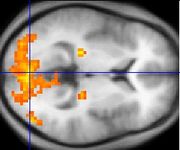

Asperger syndrome appears to result from developmental factors that affect many or all functional brain systems, as opposed to localized effects. Although the specific underpinnings of AS or factors that distinguish it from other ASDs are unknown, and no clear pathology common to individuals with AS has emerged, it is still possible that AS's mechanism is separate from other ASD. Neuroanatomical studies and the associations with teratogens strongly suggest that the mechanism includes alteration of brain development soon after conception. Abnormal migration of embryonic cells during fetal development may affect the final structure and connectivity of the brain, resulting in alterations in the neural circuits that control thought and behaviour. Several theories of mechanism are available; none are likely to be complete explanations.

The underconnectivity theory hypothesizes underfunctioning high-level neural connections and synchronization, along with an excess of low-level processes. It maps well to general-processing theories such as weak central coherence theory, which hypothesizes that a limited ability to see the big picture underlies the central disturbance in ASD. A related theory—enhanced perceptual functioning—focuses more on the superiority of locally oriented and perceptual operations in autistic individuals.

The mirror neuron system (MNS) theory hypothesizes that alterations to the development of the MNS interfere with imitation and lead to Asperger's core feature of social impairment. For example, one study found that activation is delayed in the core circuit for imitation in individuals with AS. This theory maps well to social cognition theories like the theory of mind, which hypothesizes that autistic behaviour arises from impairments in ascribing mental states to oneself and others, or hyper-systemizing, which hypothesizes that autistic individuals can systematize internal operation to handle internal events but are less effective at empathizing by handling events generated by other agents.